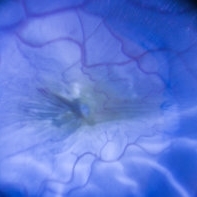

Retinal Vasculitis in Behcet's OS

Retinal Vasculitis in Behcet's OS

Jun 29 2018 by Gareth Lema, MD, PhD

IVFA at 7 minutes showing retinal vasculitis, cystoid macular edema, and disc staining.

Photographer: Ross Eye Institute, University at Buffalo Jacobs School of Medicine, Buffalo. NY

Imaging device: Optos

Condition/keywords: Behcet's Disease, cystoid macular edema (CME), disc staining, retinal vasculitis